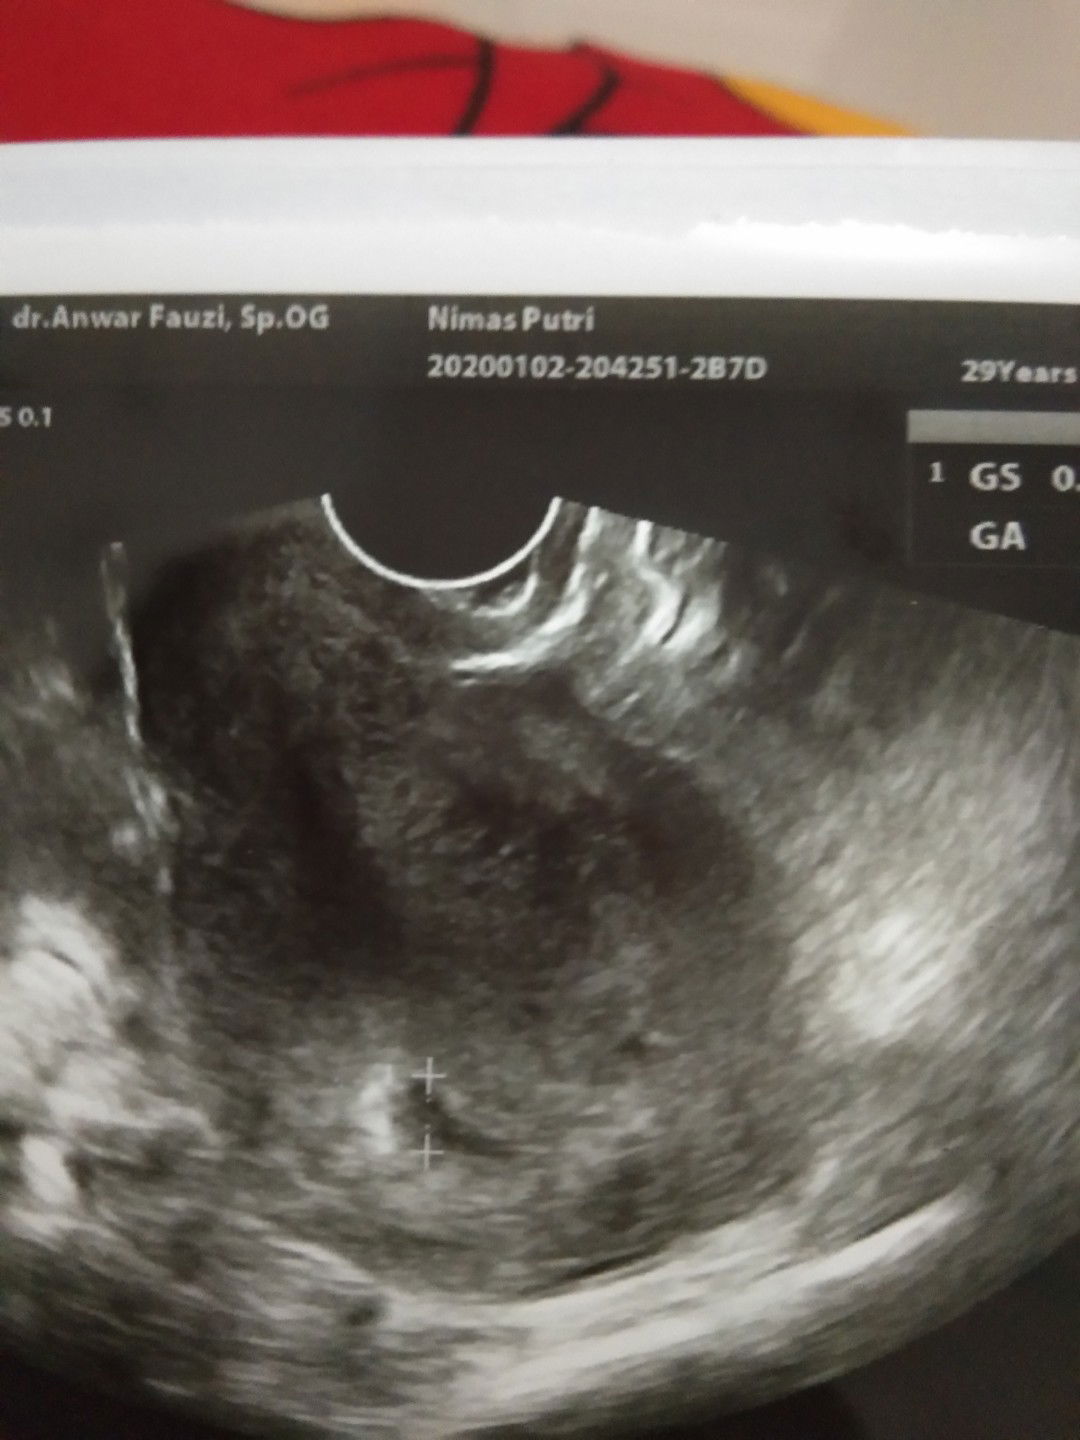

test positif tapi di usg vagina cuman terlihat penebalan dinding rahim